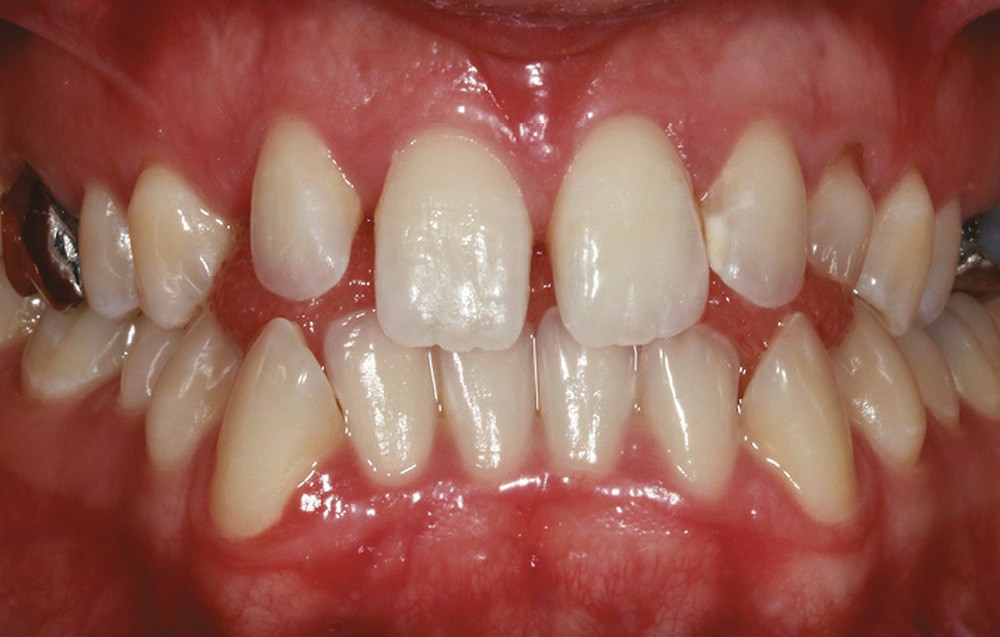

Sur le plan dentaire, on note l’absence des canines maxillaires permanentes sur l’arcade et la persistance de 63. Il existe une DDD par défaut maxillaire (indice de Bolton antérieur 90,2 %) due à l’absence des canines sur l’arcade, mais aussi à une dysharmonie de forme des dents maxillaires (fig. 2a-e).

L’examen radiologique 2D nous confirme l’inclusion de 13 et 23 en position haute, oblique en bas et en avant, couronnes en projection des apex de 11 et 21 et nous permet de quantifier le décalage squelettique (fig. 3 et 4). L‘examen radiologique 3D (cone beam) objective les rapports…